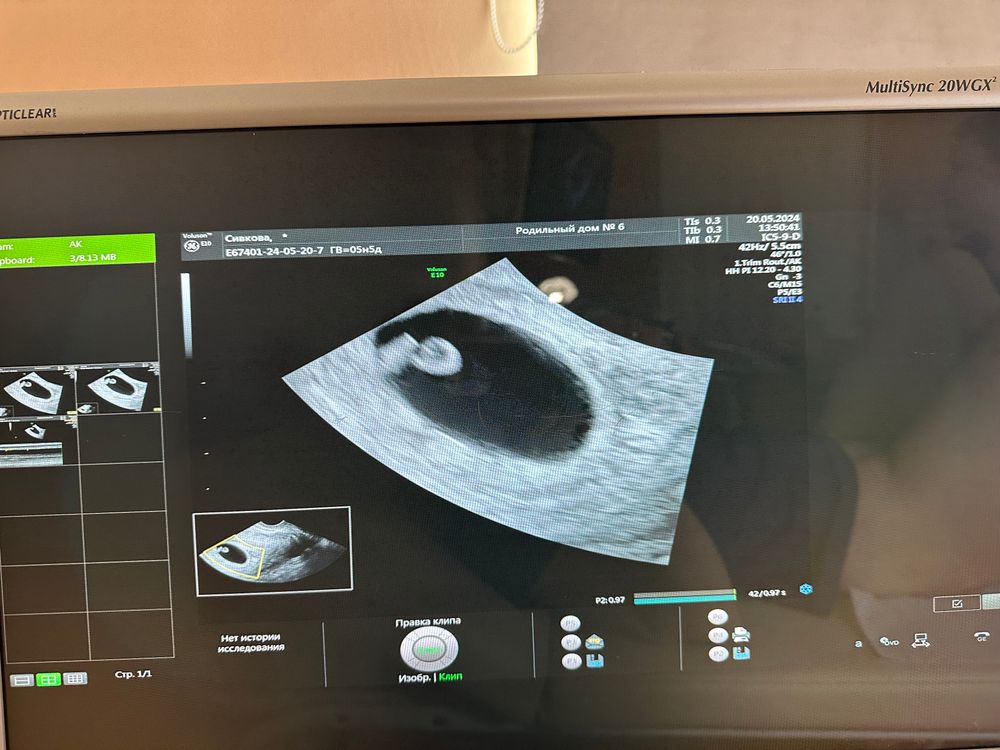

5/5 полных Нед, по узи 6/2 поставили

Pysenok , пя 7.6мм по узи срок 5н3д мешочек 2мм но вот смущают что пишут деформация